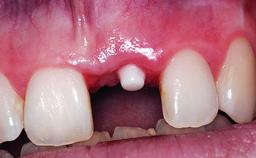

Replacement of an Upper Right Central Incisor with Root Resorption: Ridge Preservation, Delayed Placement of an NC Bone Level Roxolid Implant

A 32-year-old female Caucasian patient with a compromised maxillary right central incisor was referred to us by a general dentist. Her chief complaints were discomfort and mobility of tooth 11 with unsatisfactory esthetics due to discoloration. The patient reported a previous trauma, some years earlier, as the origin of pathology on the afflicted tooth. Anamnesis was negative for any other dental or periodontal pathology in the remaining dentition. The patient did not take any medication and reported to be a light smoker (5–10 cigs/day). She had high esthetic expectations of her treatment. The extraoral examination revealed a high smile line with full exposure of her maxillary teeth and surrounding soft tissue in the area between the second premolars.

# of Implants 1

Type of Implants Reduced-Diameter|Two-Piece